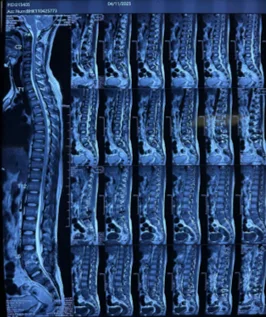

Evaluation at Bangalore Back

I begin with a clean slate—no assumptions. We review pre‑ and post‑operative MRIs, operative notes, implant position, and alignment. We add dynamic X‑rays for movement, CT for fusion/implant integrity, and MRI with metal‑artifact reduction when needed. Equally important are posture analysis, core stability testing, and rehabilitation review. This structured walk‑through reveals the true driver of pain and guides the plan.

Before & After Clinical Gallery

We showcase real patient cases (with consent), including:

- Pre- and Post-operative MRIs and X-rays

- Disc Herniations, Stenosis, and Spondylolisthesis cases

- Visible improvement in alignment and decompression